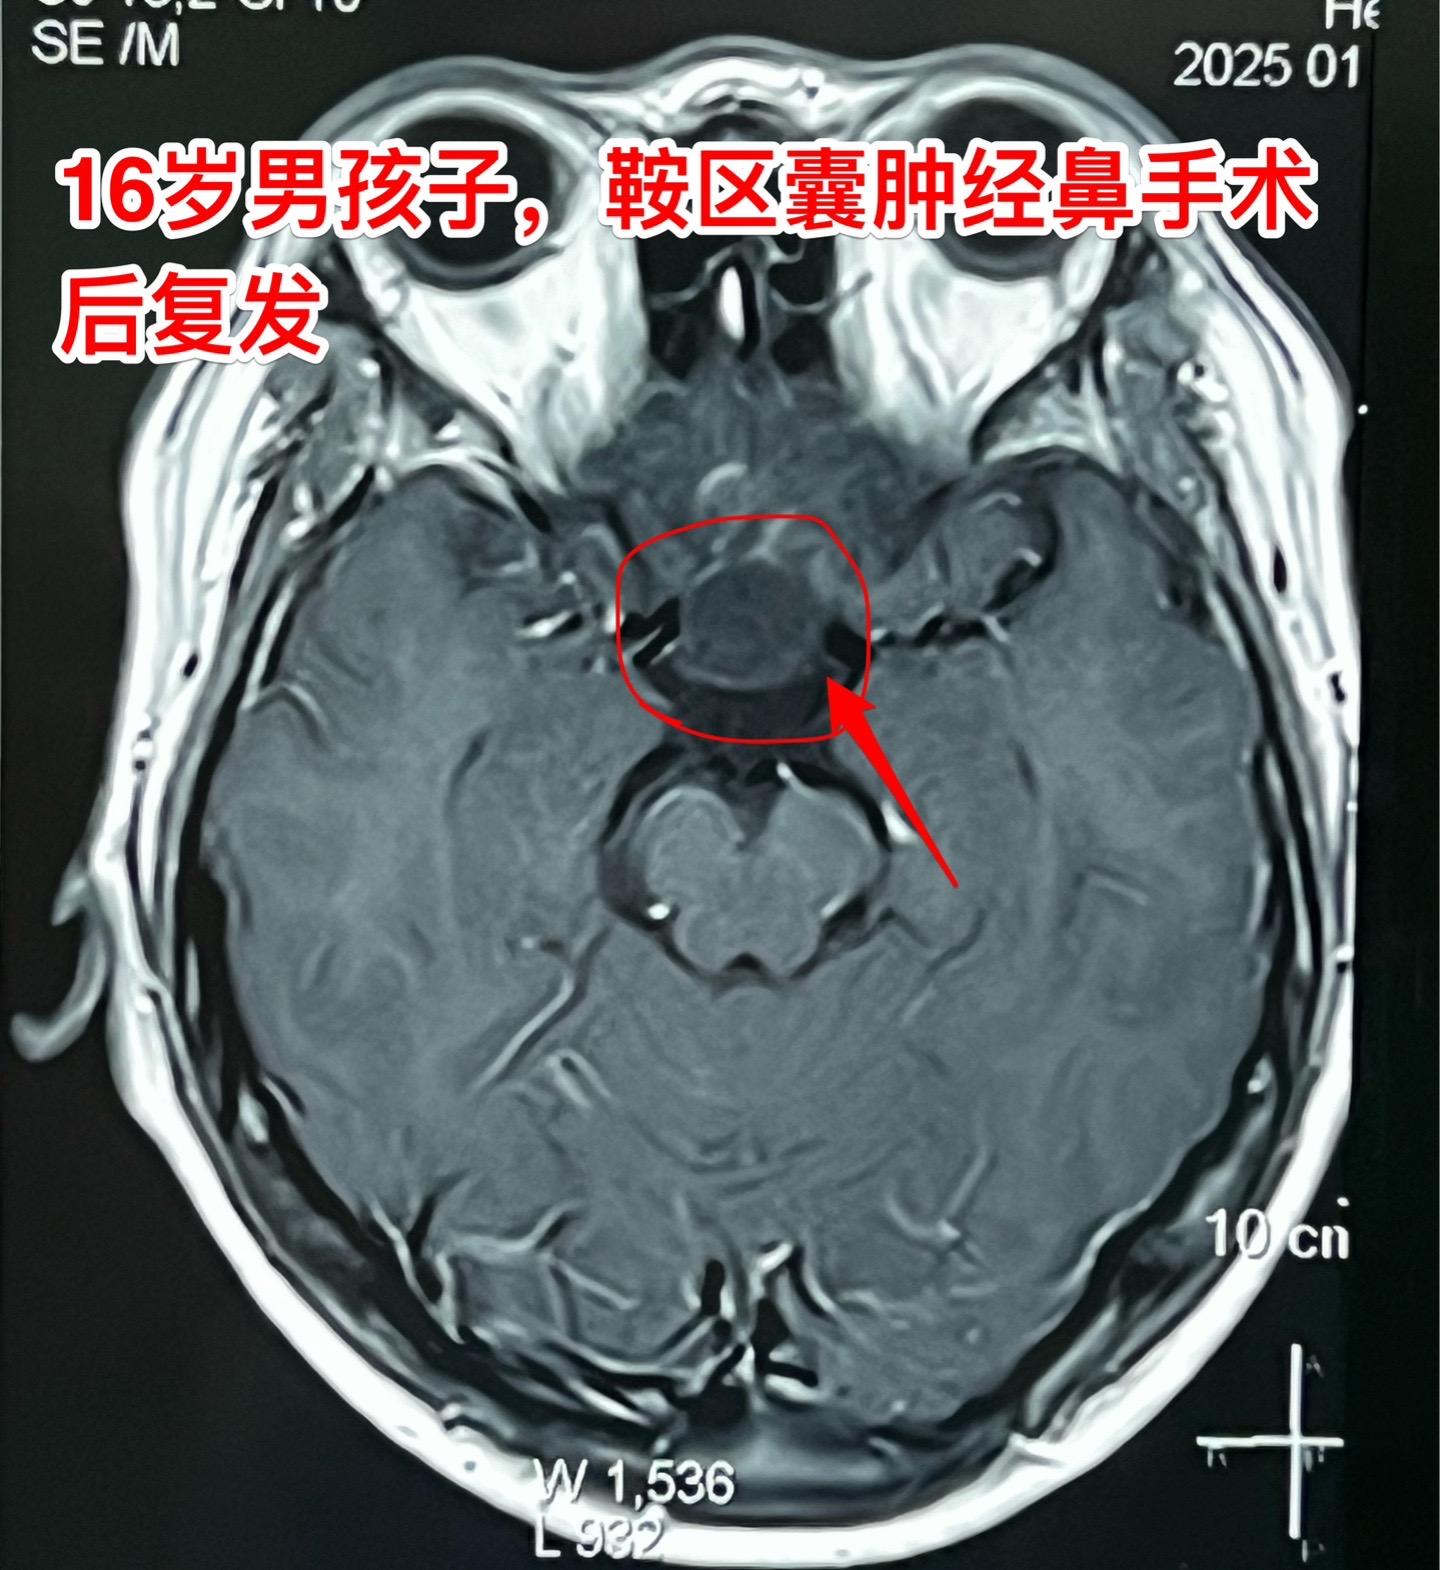

鞍区囊肿不能说是小问题(确诊拉克氏囊肿)16岁的男孩子2年前就因多饮多尿症状到医院检查发现鞍区囊肿,怀疑是拉克氏囊肿。这个病不是真性肿瘤,但是也不是小问题,也会导致尿崩症、生长发育迟缓、视力下降等问题。 他们一家选择了一个著名的医院去作手术,采用经鼻手术方式。遗憾的是手术中取得的标本最终未得出确切的病理诊断。手术后小孩子还出现了脑脊液鼻漏、颅内感染,受老罪了。 随后两年多时间内多次复查磁共振显示囊肿复发了,而且出现视力下降。然而小孩子对于第一次手术的痛苦印象太深了,故而拒绝作第